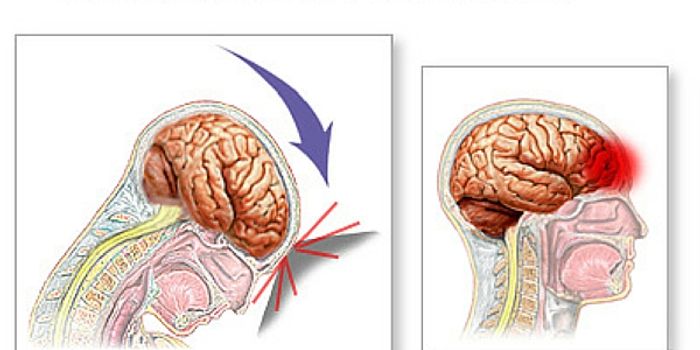

MAR 23, 2016NeuroscienceWhile the subject of brain injuries, concussion and Chronic Traumatic Encephalopathy (CTE) have swirled around the NFL f ...

JUN 04, 2018NeuroscienceA stroke is a severe medical event that impacts brain function because the supply of oxygen is cut off during a stroke. ...